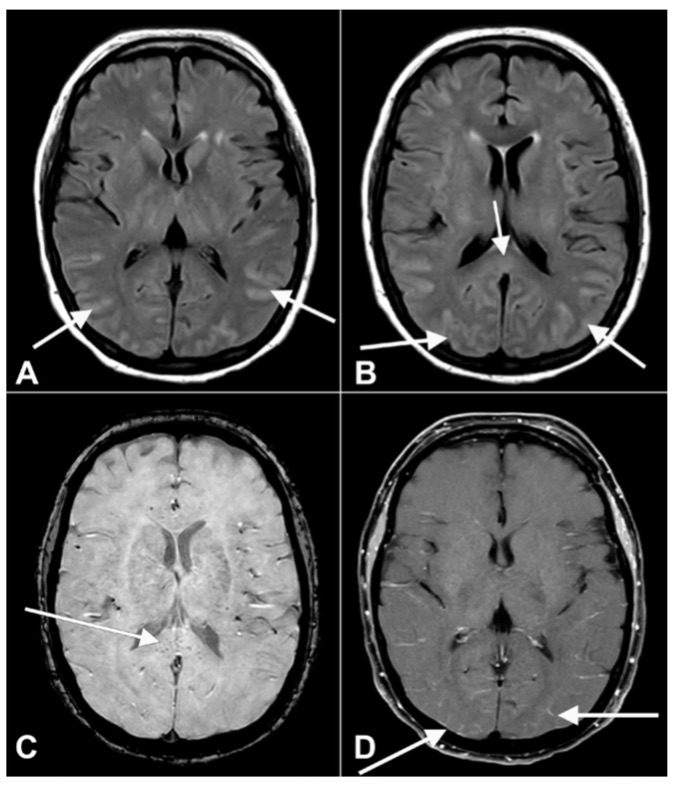

譫妄是一種嚴重的精神狀態紊亂,患者通常感到困惑、激動和無法清晰思考。值得一提的是,自COVID-19大流行以來,主要的神經系統併發症,如腦病、中風、癲癇和共濟失調均已觀察到。

此次Vlisides等人在論文則提到,譫妄似乎是一種常見的併發症。以往的調查顯示,重症監護病房(ICU)的發生率約為65%-80%。此前有研究稱,新冠病毒直接侵入中樞神經系統可導致譫妄,全身炎症反應也可進一步加重神經認知障礙。

Vlisides提到,有幾個因素在起作用。首先,COVID-19這種疾病本身會導致腦部氧氣減少、血栓形成和中風,從而導致認知障礙。此外,譫妄患者的炎症標誌物顯著增加。混亂和焦慮可能是大腦炎症的結果。